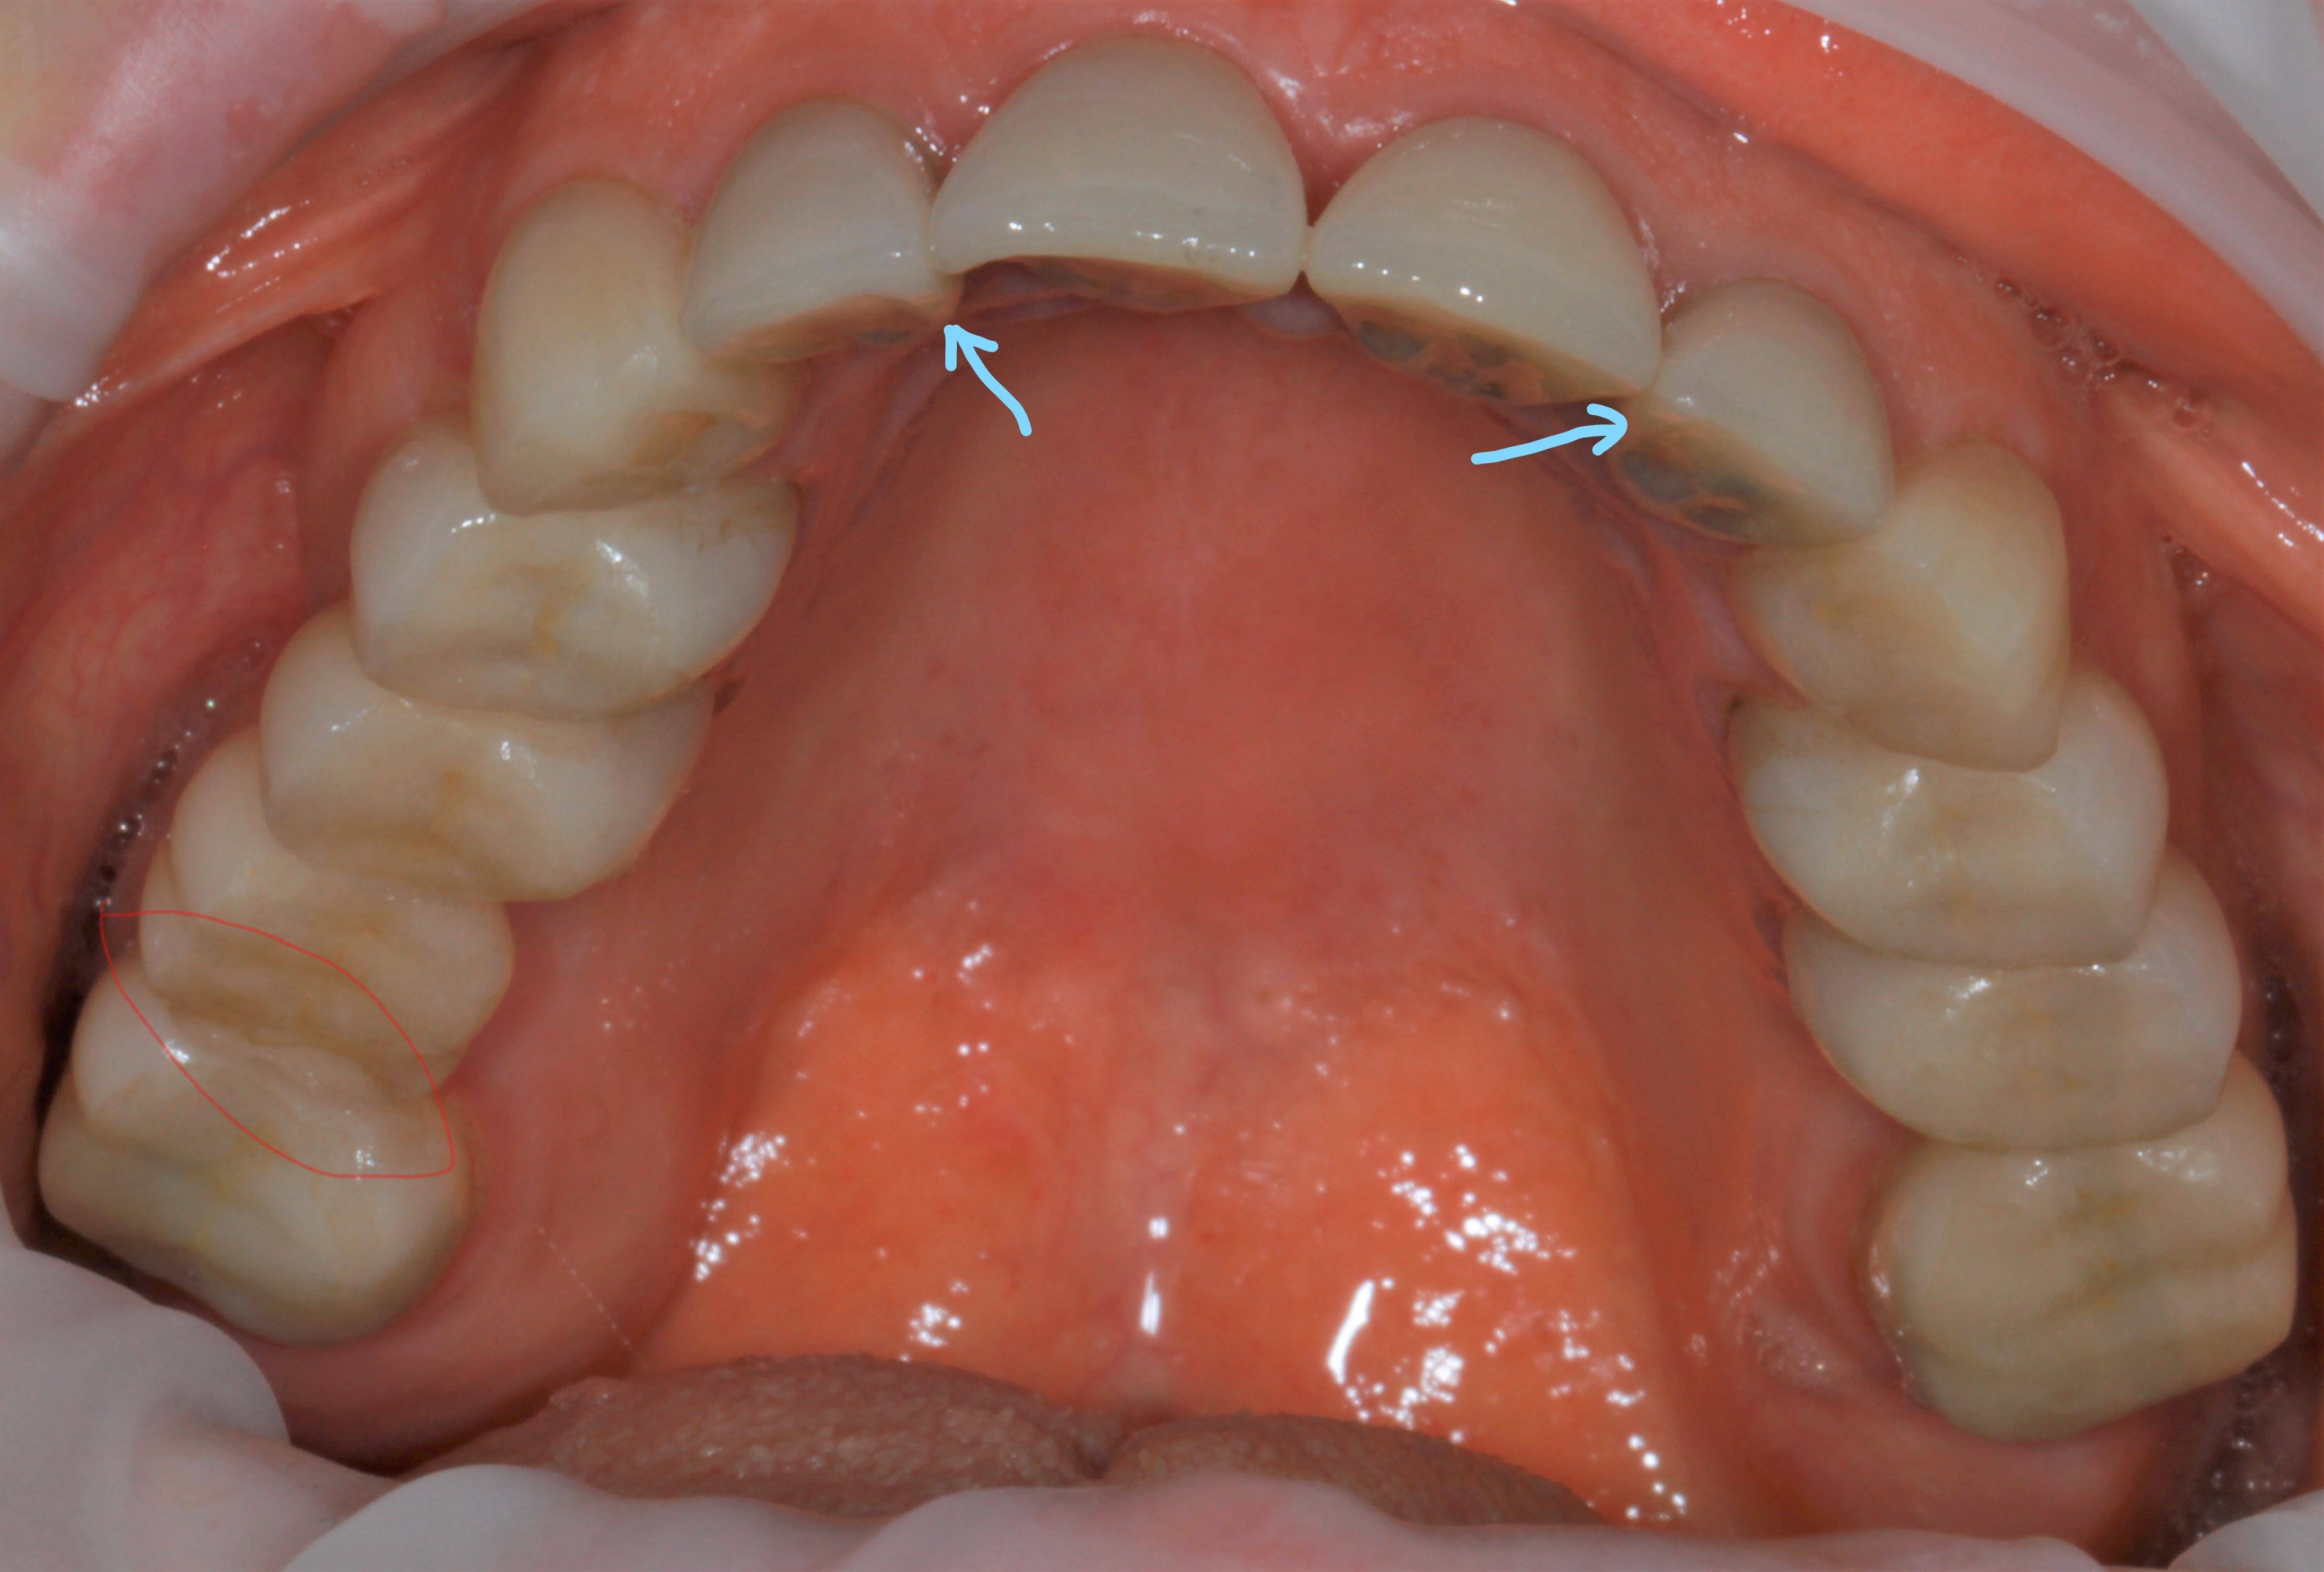

ben oui ç était prévisible , à cause des 2 flèches bleues plus haut .

ç est un grand classique ça . quand tu ne peux pas être libre devant , tu t énerves derrière .

et ç est meme pas derriere en fait , mais plutôt dans une zone la plus éloignée possible de devant .

donc ç est derrière et de coté . en diagonale , quoi .

il s avère qu en plus là, derrière , ç est nouveau bridge , donc pas encore usé à sa convenance , tout au moins en latéral .

alors elle s engatse dessus avec beaucoup de force puisque ç est tout pres de l axe charniere .

là où ç est vicieux , ç est que si ton bridge etait pipé avec une grosse erreur occlusale , ben il serait tjs là , entier .

il serait tjs là , pcq si l erreur était plus importante à l arrière ,sur un bridge à la con , elle aurait eu mal soit a l atm soit aux dents antagonistes , et elle aurait cherché un autre endroit pour aller se désénerver . en l occurrence elle t aurait fracassé le bloc ant .

alors maintenant que tu a résolu le pb post ( qui n était qu une conséquence de devant ) méfies , par sympathie pour toi , je te conseillerais de vite vite retoucher au niveau des 2 flèches bleues .

si tu ne le fais pas , tu vas encore dire que je suis un chat noir , un enlaystradamus :-))))

puis aussi la crete mesiale de la 14 coté palatin , faut retoucher .